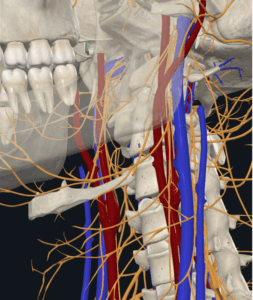

頭痛とめまいを引き起こした頭蓋頸椎の変位